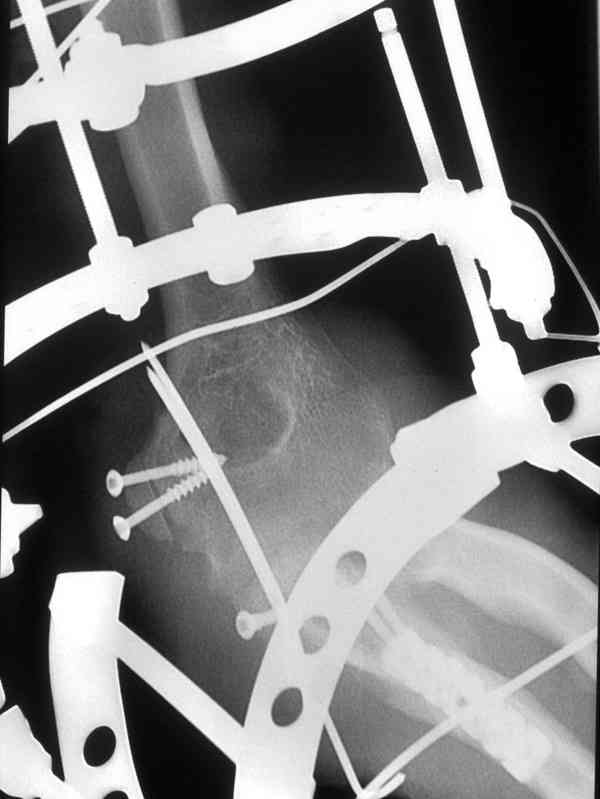

Естественно ревизия сустава и удаление рубцово-хрящевидных тканей.Затем наложили аппарат Илизарова с шарнирами. Первые 2 дня сустав был фиксирован трансартикулярно 2-мя спицами, затем спицы удалили. И больной начинает движения в аппарате.

Прилагаюся послеоперационные рентгенограммы.

Планиуем аппарат на 3-4 нед.

Что-то по снимкам ось шарниров с осью вращения локтевого сустава не сильно близко.

это больше похоже на апарат Волкова-Аганясяна...хотя я могу и ошибатся...